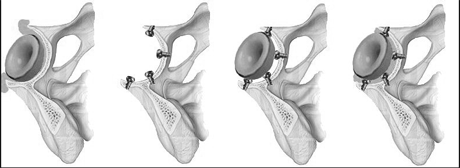

Использование современной техники цементировки при артропластике тазобедренного сустава (ТБС) показывает отличные результаты у пациентов с костным ложем, несостоятельным для выполнения бесцементной процедуры (Spotorno L. et al., 1987; Reigstat A. et al., 1988; Garino J. et al., 1997). Однако цементная техника намного сложнее, чем кажется на первый взгляд (Judet T.,1997)и «недолюбливается» некоторыми хирургами, любящими простые решения. Анализ отдаленных результатов эндопротезирования свидетельствует о довольно частом возникновении такого осложнения, как подвывих или вывих гнезда (ацетабулярного кубка) эндопротеза (Madey S.M. et al., 1997, Courpied J. P., 1998). Неправильная установка вертлужного кубка является одной из наиболее частых интраоперационных ошибок при эндопротезировании ТБС (Daly P. et al., 1992; Iorio R., 1997), приводящей к вышеуказанному расшатыванию кубка. При попытке имплантации кубка может происходить неправильная установка вертлужного компонента эндопротеза, так как хирург, производящий эндопротезирование, имея неправильные ориентиры, вынужденно «подст-раивается» под имеющееся костное ложе, пытаясь или вертикализировать кубок, или «вдавить» поглубже за счет цемента, что является недопустимой ошибкой и резко увеличивает вероятность вывихов и расшатывания импланта. На наш взгляд, неправильно подгонять эндопротез под костное ложе. Мы рекомендуем моделировать костное ложе под имплант. Многое зависит и от самого импланта. К примеру, простые гемисферические ацетабулярные кубки не имеют цементных распорок-ограничителей (спейсеры-spaeers) (рис.1), что приводит к глубокому утопанию в цементе и образованию неравномерной цементной мантии - у одной из стенок или на дне иногда кубок может контактировать с костью (рис.2а и б).

Рис. 1. Различные модели ацетабулярных кубков без цементных спейсеров